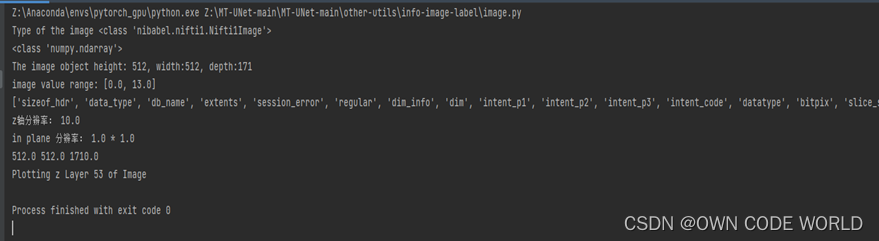

13.我们的数据train和test都是png格式的,而项目需要的原始数据是(img.nii.gz和label.nii.gz)格式的,因此首先要了解原始数据的格式。.gz是对.nii文件的压缩。而.nii文件是NIFTI格式的文件,主要包含三部分:hdr, ext, img。为了详细了解里面都有什么,通过代码的方式进行了了解:

对我来说,最有用的两个信息是:

- 512512171,因此推测,这是一个三维的数据,将512*512的切片堆叠了171份,因此按照这个推测,可以把我们png的数据集,也进行堆叠压缩转换成.nii.gz格式的数据。

- 上图是label.nii.gz的信息,可以看到image value range为[0,13],所一这也就解释了为什么训练的时候,分类的类别为14类。